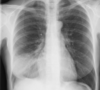

Pneumothorax

Raised hemidiaphragm (phrenic nerve injury) due to lung cancer